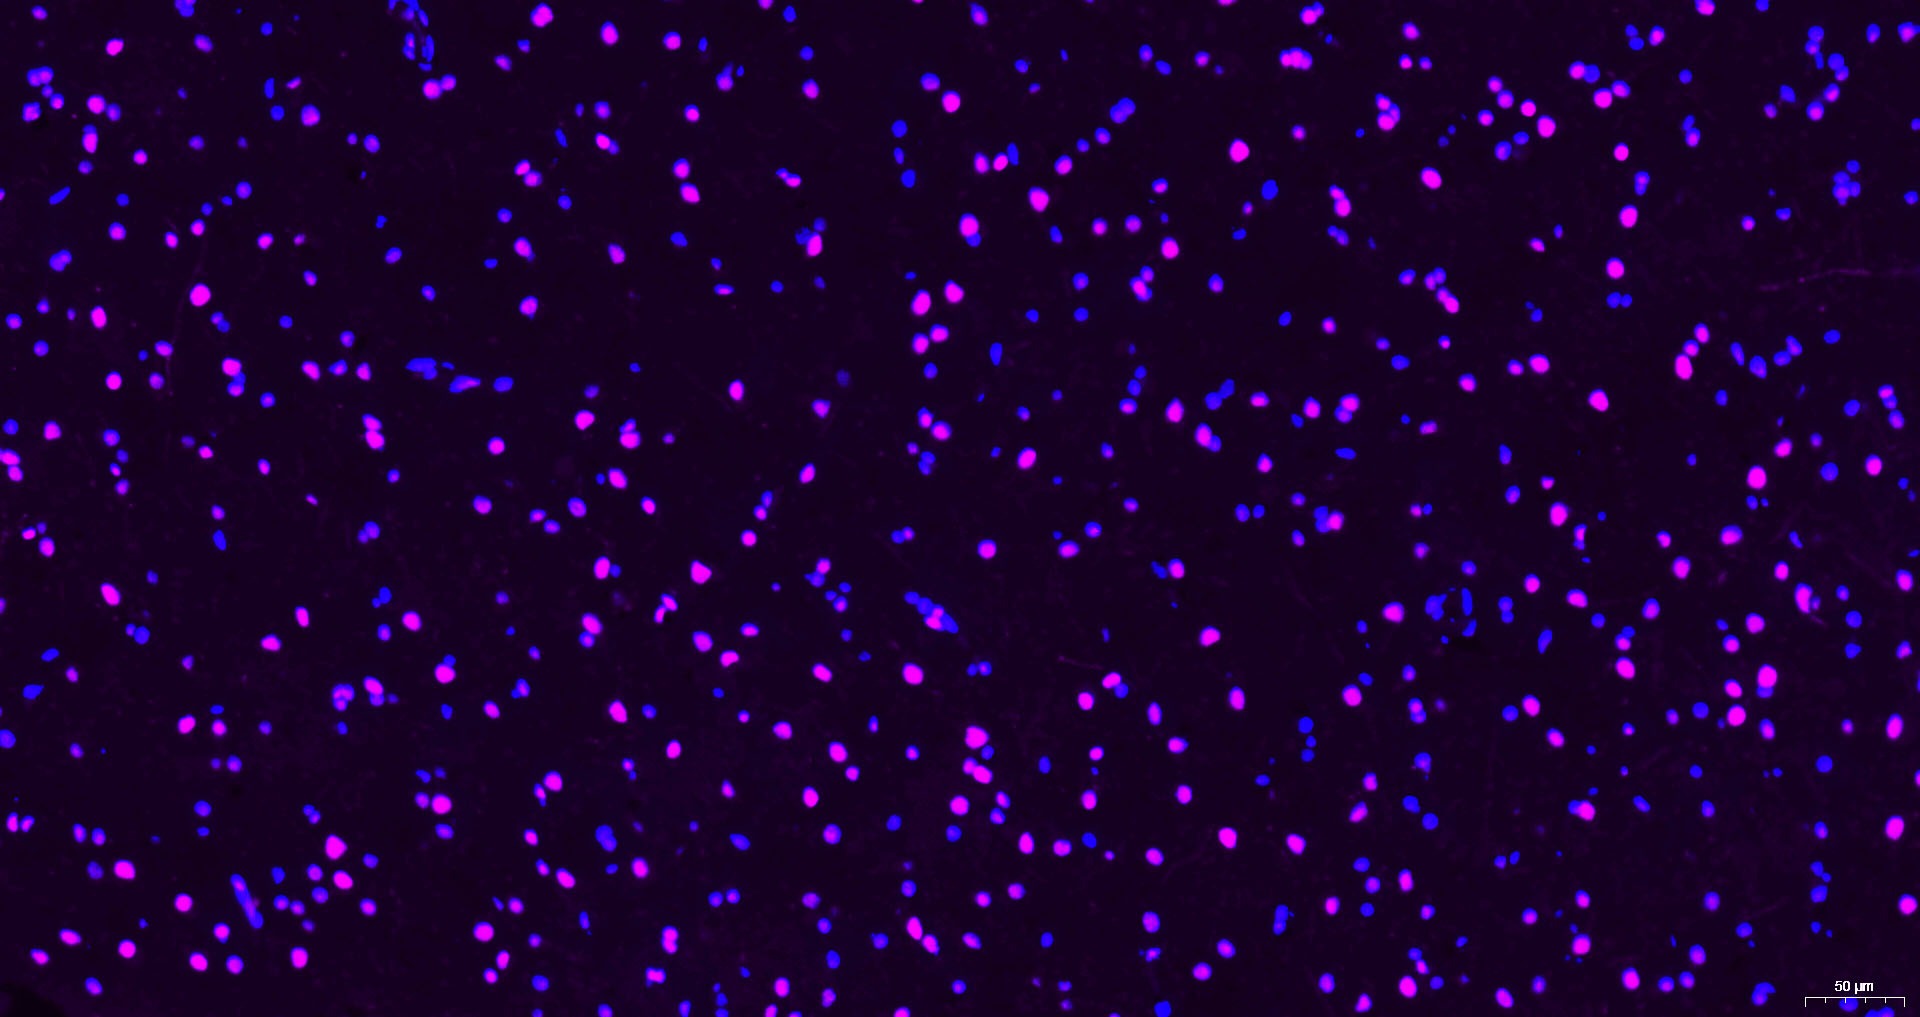

2. Paraformaldehyde-fixed, paraffin embedded Rat Cerebrum; Antigen retrieval by boiling in sodium citrate buffer (pH6.0) for 15 min; Antibody incubation with Histone H3 Monoclonal Antibody, Unconjugated at 1:200 overnight at 4°C. Followed by conjugated Goat Anti-Mouse IgG antibody (Purple, TMAB-02010C5), DAPI (blue) was used to stain the cell nuclei. 3. Paraformaldehyde-fixed, paraffin embedded Mouse Cerebrum; Antigen retrieval by boiling in sodium citrate buffer (pH6.0) for 15 min; Antibody incubation with Histone H3 Monoclonal Antibody, Unconjugated at 1:200 overnight at 4°C. Followed by conjugated Goat Anti-Mouse IgG antibody (Purple, TMAB-02010C5), DAPI (blue) was used to stain the cell nuclei. 4. Paraformaldehyde-fixed, paraffin embedded Human Cerebrum; Antigen retrieval by boiling in sodium citrate buffer (pH6.0) for 15 min; Antibody incubation with Histone H3 Monoclonal Antibody, Unconjugated at 1:200 overnight at 4°C. Followed by conjugated Goat Anti-Mouse IgG antibody (Purple, TMAB-02010C5), DAPI (blue) was used to stain the cell nuclei. 5. Paraformaldehyde-fixed, paraffin embedded Mouse Testicles; Antigen retrieval by boiling in sodium citrate buffer (pH6.0) for 15 min; Antibody incubation with Histone H3 Monoclonal Antibody, Unconjugated at 1:200 overnight at 4°C. Followed by conjugated Goat Anti-Mouse IgG antibody (Purple, TMAB-02010C5), DAPI (blue) was used to stain the cell nuclei. 6. Paraformaldehyde-fixed, paraffin embedded Human Liver; Antigen retrieval by boiling in sodium citrate buffer (pH6.0) for 15 min; Antibody incubation with Histone H3 Monoclonal Antibody, Unconjugated at 1:200 overnight at 4°C. Followed by conjugated Goat Anti-Mouse IgG antibody (Purple, TMAB-02010C5), DAPI (blue) was used to stain the cell nuclei. 7. Paraformaldehyde-fixed, paraffin embedded Human Kidney; Antigen retrieval by boiling in sodium citrate buffer (pH6.0) for 15 min; Antibody incubation with Histone H3 Monoclonal Antibody, Unconjugated at 1:200 overnight at 4°C. Followed by conjugated Goat Anti-Mouse IgG antibody (Purple, TMAB-02010C5), DAPI (blue) was used to stain the cell nuclei. 8. Paraformaldehyde-fixed, paraffin embedded Human Colon; Antigen retrieval by boiling in sodium citrate buffer (pH6.0) for 15 min; Antibody incubation with Histone H3 Monoclonal Antibody, Unconjugated at 1:200 overnight at 4°C. Followed by conjugated Goat Anti-Mouse IgG antibody (Purple, TMAB-02010C5), DAPI (blue) was used to stain the cell nuclei. ![]() ![]() ![]() ![]() ![]() ![]() ![]() ![]() |